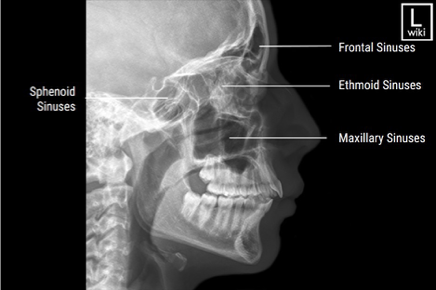

Lateral Projection of Paranasal Sinuses

PA Axial of the Frontal and Ethmoidal Sinuses - Caldwell Method

Submentovertical of Ethmoidal & Sphenoidal Sinuses

Parietoacanthial of the Maxillary and sphenoidal sinuses - open-mouth waters method

Parietoacanthial projection of the maxillary sinuses - Waters Method

Lateral of the sinuses

PA axial of the frontal and ethmoidal sinuses (Caldwell Method)

Parietoacanthial of the maxillary sinuses (Waters Method)

Parietoacanthial of the maxillary and sphenoidal sinuses (Open-mouth waters method)

Submentovertical of the ethmoidal and sphenoidal sinuses